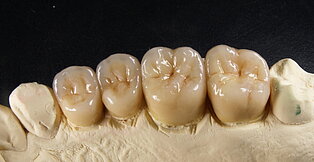

Keramikstufen